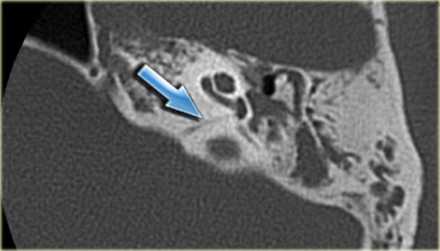

Хроническое воспаление среднего уха с холестеатомой: коронарная КТ показывает боковой свищ полукруглого канала (стрелка), вызванный эрозией кости из-за роста новообразования